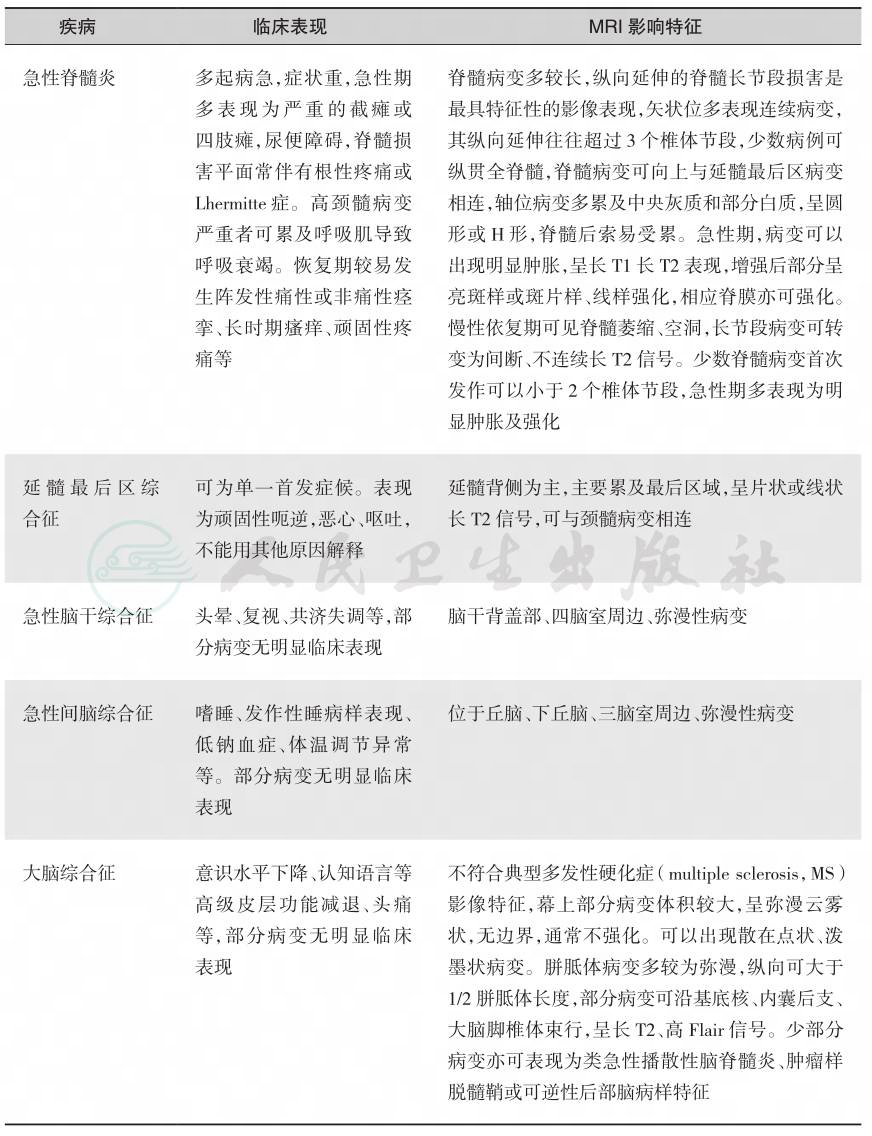

其中,延髓最后区综合征仅表现为顽固性呃逆、恶心、呕吐,不能用其他原因解释。该病诊断需要以病史、核心临床症候及影像特征为基本依据,以AQP4-IgG诊断分层,同时需要排除其他疾病可能(表2)。

表2 成人NMOSD诊断标准(IPND,2015年)

NMOSD:视神经脊髓炎谱系疾病;AQP4-IgG:水通道蛋白4抗体;LETM:长节段横贯性脊髓炎(longitudinally extensive transverse myelitis)

AQP4-IgG阳性的NMOSD诊断标准 (1)至少1项核心临床特征 (2)用可靠的方法检测AQP4-IgG阳性(推荐CBA法) (3)排除其他诊断 AQP4-IgG阴性或AQP4-IgG未知状态的NMOSD诊断标准 (1)在1次或多次临床发作中,至少2项核心临床特征并满足下列全部条件:①至少1项临床核心 特征为视神经炎、急性LETM或延髓最后区综合征;②空间多发(2个或以上不同的临床核心特 征);③满足MRI附加条件 (2)用可靠的方法检测AQP4-IgG阴性或未检测 (3)排除其他诊断 核心临床特征 (1)视神经炎 (2)急性脊髓炎 (3)最后区综合征,无其他原因能解释的发作性呃逆、恶心、呕吐 (4)其他脑干综合征 (5)症状性发作性睡病、间脑综合征,脑MRI有NMOSD特征性间脑病变 (6)大脑综合征伴NMOSD特征性大脑病变 AQP4-IgG阴性或未知状态下的NMOSD MRI附加条件 (1)急性视神经炎:脑MRI有下列之一表现:①脑MRI正常或仅有非特异性白质病变;②视神经长 T2信号或T1增强信号>1/2视神经长度或病变累及视交叉 (2)急性脊髓炎:长脊髓病变>3个连续椎体节段或有脊髓炎病史的患者相应脊髓萎缩>3个连续椎 体节段 (3)最后区综合征:延髓背侧/最后区病变 (4)急性脑干综合征:脑干室管膜周围病变 |